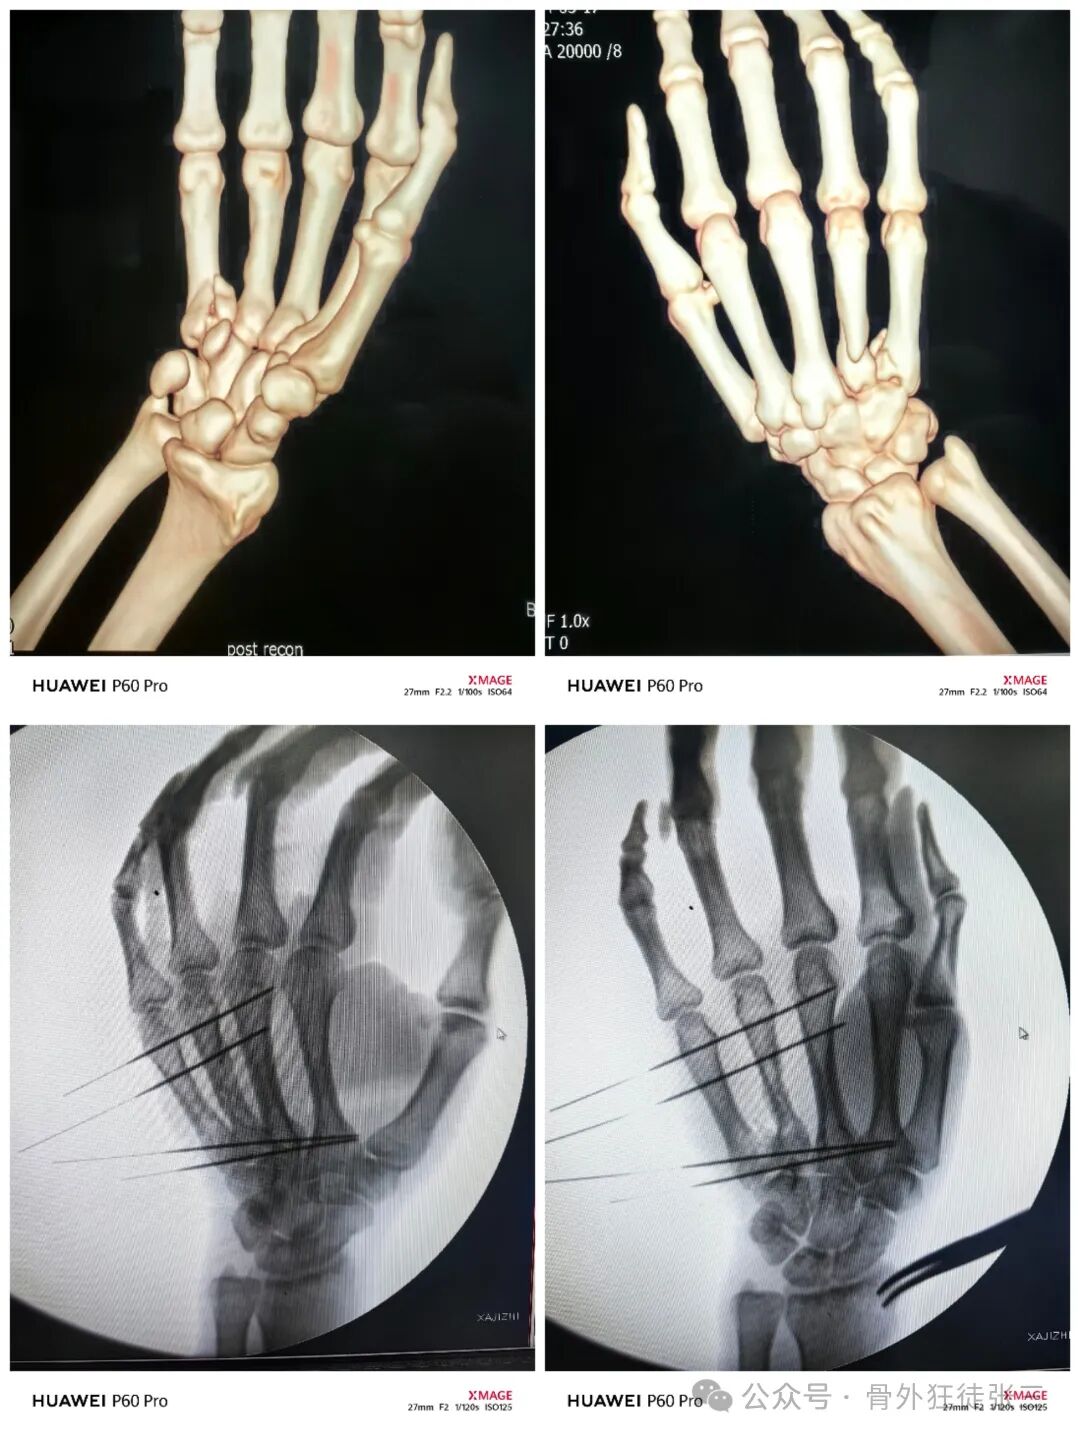

第一掌骨骨折占所有掌骨骨折的25%,仅次于第五掌骨,其中基底骨折占比高达80%。第一掌骨骨折包括Bennett(斜行关节内骨折)Winterstein(关节外横行骨折)、Rolando(Y/T形粉碎骨折)。因其解剖复杂、生物力学特殊及功能恢复要求严苛,成为手外科治疗难点。

传统切开复位内固定虽能提供稳定固定,但创伤大、软组织干扰多,而克氏针支架技术凭借其微创、灵活、可早期功能锻炼的优势,逐渐成为重要选择。

本文通过7例典型病例,展示克氏针支架在不同类型第一掌骨基底骨折中的应用。

一、Bennett骨折

经皮闭合复位,横向克氏针固定于第二掌骨+斜针固定第一腕掌关节,书上甚至用了两枚细螺钉。

固定方式,采用经皮复位。两枚克氏针(Iselin技术)横向固定,不固定关节,书上原图有一枚斜针固定第一腕掌关节,针尾可以交锁使用小针夹或者骨水泥或者弹力手套等。